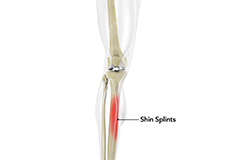

Shin Splints

Shin splints are pain and inflammation of the tendons, muscles and bone tissue along the tibia or shinbone (lower leg). It occurs because of vigorous physical activities such as exercise or sports.